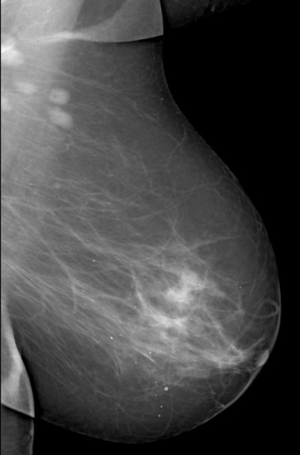

Аномалии молочной железы: медицинские примеры и визуализация